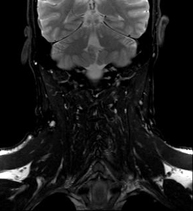

- Neck MRI

This non-invasive diagnostic procedure uses an electromagnetic field and radio waves (from a transmitter and receiver) to acquire high-definition anatomical images of the neck. It is a radiation-free procedure. Indicated for: suspected tumours, infections, lymph nodes.